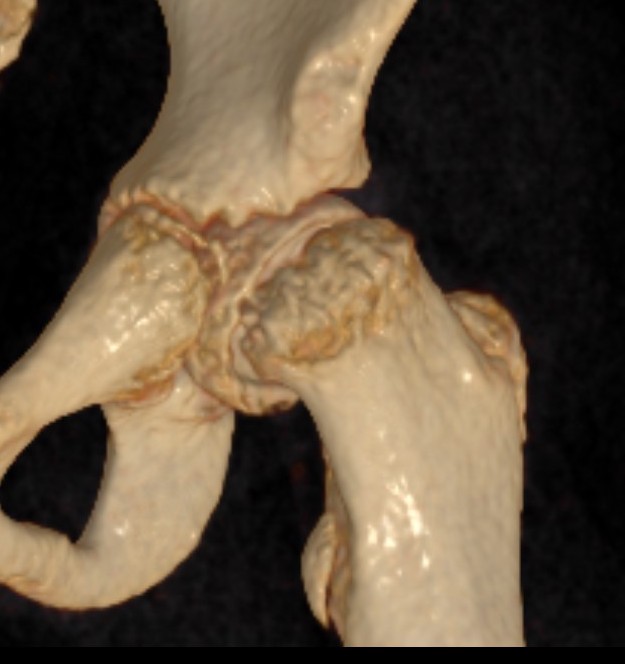

Southwick classification

Southwick Angle / Slip Angle

- epiphyseal-diaphyseal angle on frog leg lateral

- mild <30°

- moderate 30- 50°

- severe >50°

Mild Moderate Severe